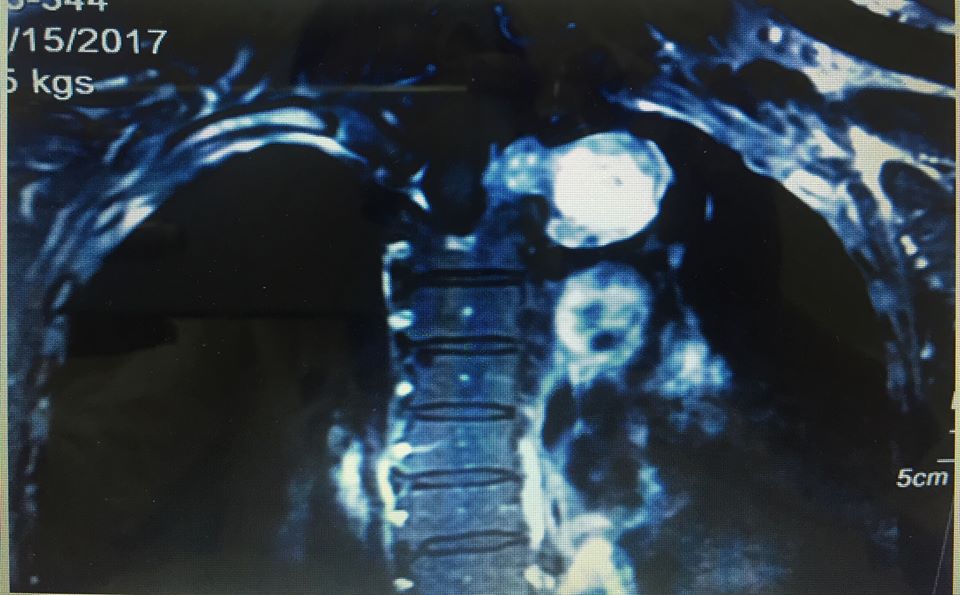

Bệnh nhân Hứa Thị Y., 61 tuổi, nhập viện trong tình trạng tức ngực kéo dài, đau lưng và vai tay trong gần một năm. Hóa ra, bệnh nhân có khối u hình ... quả tạ. Bệnh viện K Trung ương vừa phẫu thuật thành công cho bệnh nhân nữ 61 tuổi này.

Khối u "quả tạ" trong lồng ngực bệnh nhân Y. (Ảnh BSCC)

Trước đó, bệnh nhân Hứa Thị Y., 61 tuổi, nhập viện trong tình trạng tức ngực kéo dài, đau lưng và vai tay trong gần một năm, đã điều trị nhiều nơi nhưng không hiệu quả. Bệnh nhân đến khám tại Bệnh viện K Trung ương, được chẩn đoán là u thần kinh tủy sống, chỉ định phẫu thuật loại bỏ khối u nhằm giải phóng chèn ép tủy và chèn ép khoang trung thất.

Sau khi hội chẩn, các chuyên gia ung bướu trong bệnh viện, các bác sĩ nhận định đây là ca mổ phức tạp vì khối u hình quả tạ vừa nằm trong ống tủy ngực vừa nằm trong lồng ngực liên quan đến nhiều chức năng quan trọng như: vận động, cảm giác, phổi, buồng tim, các tĩnh mạch và động mạch lớn xuất phát từ tim.